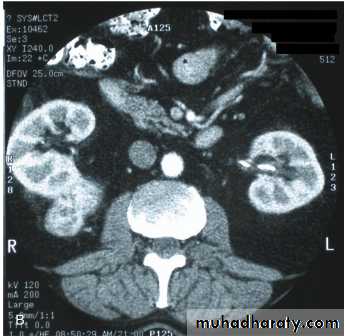

Ct scan

Ct enhanced

Rt renal mass (RCC enhanced) needs radical nephrectomyWhat this?